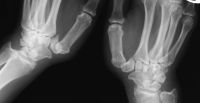

| Preop basal joint stress

views showing subluxation and subsidence: |